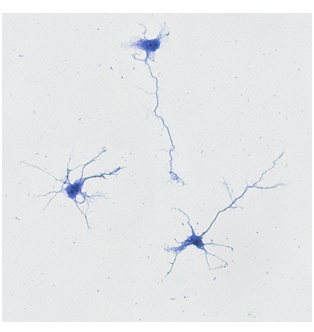

Neurotrophic support of donepezil in cortical neurons

Donepezil: Neurotrophic effect on primary cortical neurons culture